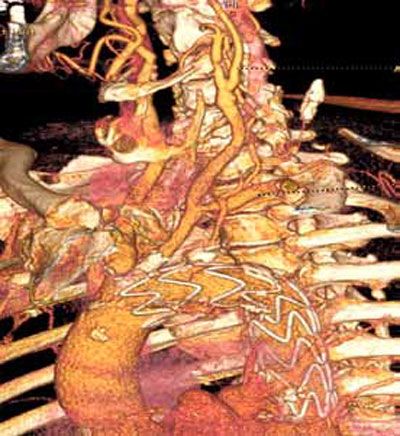

Perkutana transluminalna angioplastika sa stentom zbog aterosklerotične stenoze (90%) desne subklavijalne i desne vertebralne arterije

Dislokacija aterosklerotičnog plaka pri implantaciji aortnog stent grafta, sa stenozom leve zajedničke karotidne arterije u koju je transponirana leva subklavijalna arterija u sklopu hybrid procedure.

Dilatacija orificijuma leve zajedničke arterije sa implantacijom stenta.